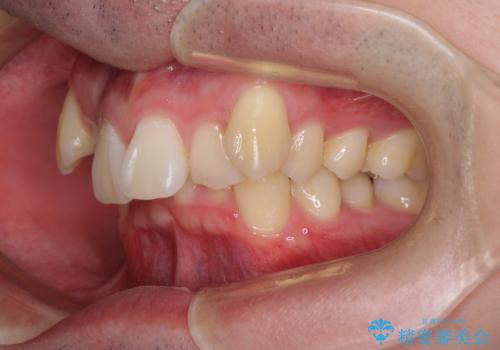

- 八重歯を気にして来院された患者様です。

顕著な上顎の八重歯とディープバイトであったため、上顎の左右第一小臼歯を抜歯することとしました。

犬歯歯根の位置や奥歯の咬み合わせから、ワイヤー装置での治療を強くおすすめいたしましたが、ご本人の強い希望により、妥協的な仕上がりとなることを了解いただき、インビザラインにて矯正治療を行うこととしました。

インビザライン単体で、左右ともに移動の難しい位置に歯根のある犬歯を整えるのは困難と判断し、補助装置を併用することとしました。